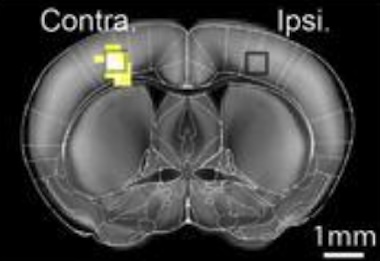

In trials studying stimulus-evoked brain responses in mice, HyFMRI successfully recorded cell-type-specific calcium signaling alongside whole-brain hemodynamics, revealing new details of how astrocytes are involved in coupling neuronal activity to localized changes in blood flow.

The project's solution was to incorporate a fiberscope-based optical imaging module and a custom surface radiofrequency coil into the bore of a preclinical MRI scanner, using custom 3D-printed components where necessary to bridge the two modalities.